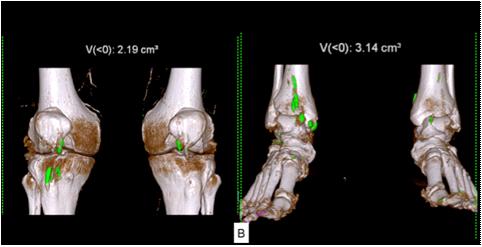

Majority of the patients had abnormal appearances of the HP region on MRI (Table 5) (Figs 1&2). Empty sella with varying thickness of the remaining pituitary tissue was the commonest abnormality noted (28 patients, 52.8% of the cohort). Only 3 patients (5.66%) had apparently normal looking HP region. Hypophysitis was diagnosed retrospectively in 1 lady with ES, whose previous MRI was consistent with hypophysitis11. One male with hypophysitis

Pituitary macroadenoma (n=9) Sellar mass with/without supra & parasellar extension and heterogenous contrast enhancement

Sequel of pituitary Enlarged sella with residual surgery (n=3) tissue and fibrotic changes with deviation of stalk: 3